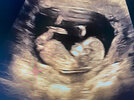

Ktoś potrafi z tych zdjęć określić płeć ? :)

Ps. Lekarz powiedział ze jakby miał obstawiać to dziewczynka ale z tego „ siusiaka „ może być jeszcze chłopak 🙈

Moim

Zdaniem chłopak bo mam podobne zdjęcia niba pod tym kątem. Na prenatalnych lekarka nie chciał strzelać bo mówi ze to za wczesnie ale ze jak będzie dziewczynka mam zadzwonić. Tydzień później inny lekarz chłopca stwierdził.